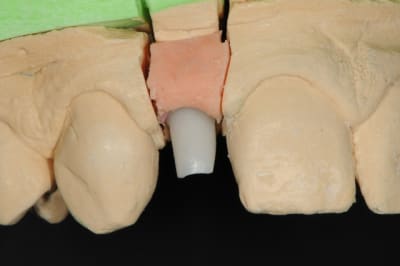

01/09/2010 à 16h54

-1 ou 2 mois plus tard ( je sais plus)

- empreinte avec transfert pop in

- pilier zircone esthétique Axiom

- prothèse et pilier

- pilier zircone en place

- couronne en place (petite compression gingivale)

fin du traitement